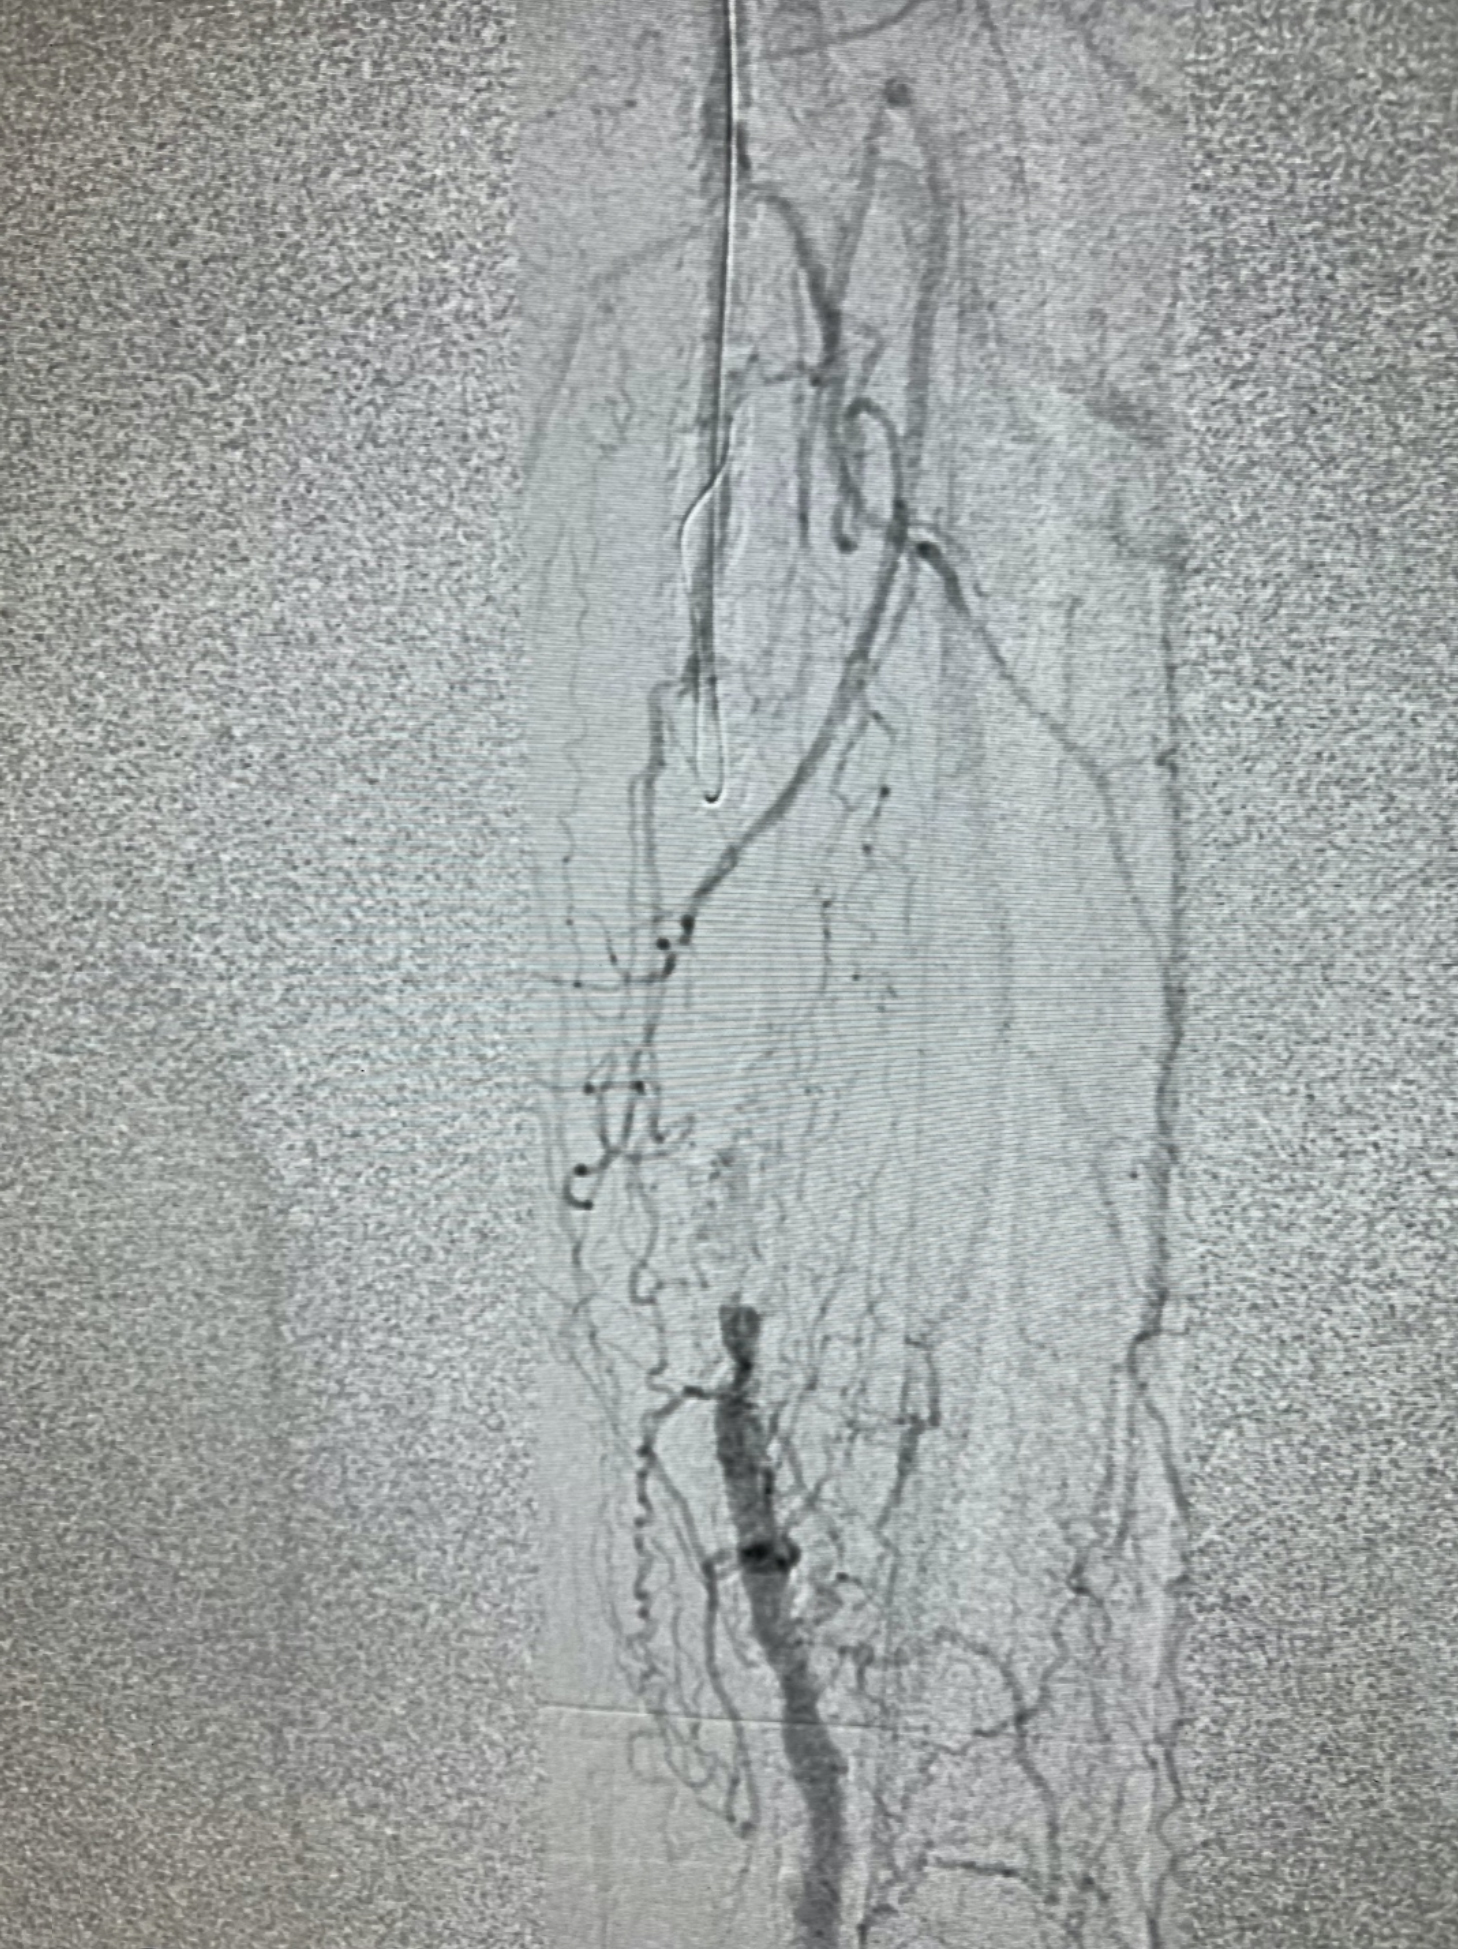

We obtained access of the right common femoral artery (CFA) under ultrasound guidance. We proceeded to perform an aortogram that showed that the inflow vessels were patent. Then a left lower extremity angiogram showed a chronic total occlusion in the left SFA (Figure 1). We started by placing a 7Fr x 45cm sheath up and over into the left CFA. We were able to cross the CTO with moderate difficulty. IVUS was then used to evaluate the plaque morphology and appropriately size the vessel. Given the extent of calcification we decided to use a 7mm x 60mm Shockwave M5+ balloon to perform IVL (Figure 2 and Figure 3). We followed this with DCB angioplasty with a 7mm x200mm Ranger (Boston Scientific). Follow-up angiography showed excellent flow with no residual stenosis (Figure 4). We were satisfied with the results and terminated the procedure. The patient did very well during and after the procedure. He was seen in follow-up and his ulcer is almost completely healed.